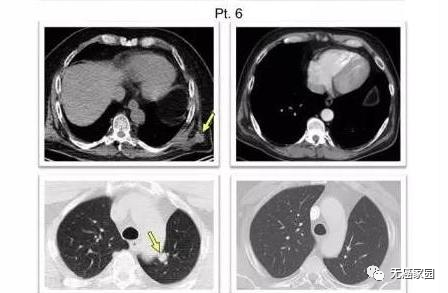

研究中的第6例患者,在疫苗治疗1周CT扫描显示左侧外侧和后侧胸壁有多个软组织结节(黄色箭头所指),接受疫苗治疗16.5周CT扫描显示:所有病灶的完全间隔消退。